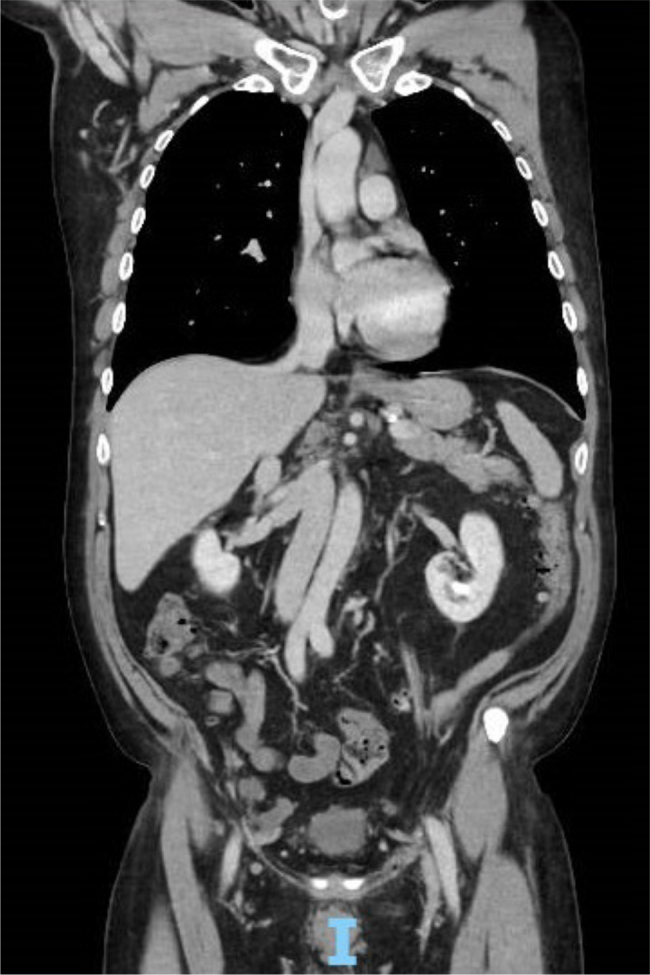

Background: Congenital anomalies of the inferior vena cava (IVC), such as interrupted or azygos continuation, complicate catheter-based procedures like atrioventricular nodal reentrant tachycardia (AVNRT) ablation. Understanding IVC variations is crucial for successful outcomes in interventional cardiology.

Case presentation: A 57-year-old male with long-standing paroxysmal atrial fibrillation (AF) underwent successful catheter ablation for AVNRT. Intra-procedurally, a congenital IVC anomaly was identified, requiring modified vascular access.

Conclusion: Recognizing IVC anomalies and adapting access strategies are key to overcoming procedural challenges and ensuring successful ablation outcomes. Comprehensive imaging and planning are vital for managing patients with IVC variations.

Learning points: Congenital inferior vena cava (IVC) anomalies, including azygos continuation, can complicate catheter-based interventions such as ablation of atrioventricular nodal reentrant tachycardia.Congenital anomalies of IVC are rare but critical considerations for atrioventricular nodal reentry tachycardia (AVNRT) ablation procedures.Understanding these variations is essential for ensuring successful catheter-based interventions and minimizing the risk of complications.